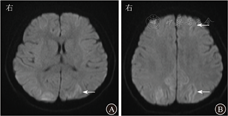

患儿男,6岁1个月,因"咳嗽、喘息3 d,加重伴嗜睡半天"于2019年9月29日入郑州大学附属儿童医院。患病以来,患儿精神差,食欲差,大小便未见明显异常。有反复咳嗽、喘息病史,入院前半个月患儿有肺炎病史,否认肝炎、结核等传染性疾病史及传染病接触史,已接种乙型肝炎疫苗、卡介苗、百白破混合疫苗、脊髓灰质炎灭活疫苗、麻疹减毒活疫苗等;患儿为第2胎第2产,足月顺产,姐体健,否认有家族性遗传病史。入院体格检查:体温为38.5 ℃,脉搏为175次/min,呼吸为42次/min,血压为99/63 mmHg(1 mmHg=0.133 kPa);呈浅昏迷,压眶皱眉,全身皮肤、黏膜无苍白、发花等,弹性正常;浅表淋巴结未触及肿大;双侧瞳孔等大,直径约3 mm,对光反射灵敏;在鼻导管吸氧下口周明显发绀,口腔黏膜光滑,咽充血,扁桃体Ⅱ度肿大,未见脓苔;颈软无抵抗,呼吸促,鼻翼煽动、三凹征阳性,双肺可闻及大量喘鸣音及中细湿啰音;心音有力、律齐,未闻及杂音;腹部软,稍膨隆,未扪及包块,肝脾肋下未及。四肢末梢暖,下肢无水肿,毛细血管再充盈时间为2 s,手足、肛周未见疱疹。膝腱反射和腹壁反射均未引出,四肢肌张力低,肌力3级,双侧巴宾斯基征、布鲁津斯基征、克尼格征均阴性。入院后初步诊断:重症肺炎,呼吸衰竭;中毒性脑病?病毒性脑炎?血常规检查:白细胞计数为10.28×109/L,血小板计数为356×109/L,中性粒细胞比例为0.81,淋巴细胞比例为0.12,CRP为1.50 mg/L,ESR为35 mm/1 h,降钙素原为0.09 μg/L。动脉血气分析:二氧化碳分压为36.6 mmHg,氧分压为56.6 mmHg。血生物化学检查:乳酸脱氢酶为119 U/L,肌酸激酶为10.06 μg/L,CK-MB为1 823 μg/L,肌钙蛋白为0.094 μg/L,B型钠尿肽前体为1 029 ng/L,血尿素氮为4.9 mmol/L,血肌酐为10.6 μmol/L。肝功能检查:总胆红素为13 μmol/L,DBil为7 μmol/L,ALT为22.3 U/L,AST为29.6 U/L,总蛋白为59 g/L,白蛋白为38 g/L。钾为3.7 mmol/L,钠为134 mmol/L,离子钙为1.20 mmol/L,氯为99 mmol/L,血糖为6.9 mmol/L,乳酸为1.2 mmol/L。血培养阴性,细菌毒素动态定量检测<5 ng/L,血清EB病毒早期抗原IgG和EB病毒衣壳抗原IgM均阳性,EB病毒衣壳抗原IgG和核抗原IgG均阴性,EB病毒DNA为3.28×105拷贝/mL。脑脊液压力为1.4 kPa,脑脊液常规检查:无色、清晰、透明,潘氏试验阴性,白细胞计数为0.095×109/L。脑脊液生物化学检查:氯为125.0 mmol/L,葡萄糖为3.0 mmol/L,蛋白质为277.9 mg/L,脑脊液腺苷脱氨酶为0.6 U/L。脑脊液EB病毒核酸DNA为5.61×106拷贝/mL。血液中S100蛋白为7.05 μg/L,神经元特异性烯醇化酶为75.25 μg/L。床边胸部X线片(图1)提示肺炎。床边脑电图检查:背景节律广泛漫波化异常,频发弥漫性慢波。入院第2天头颅MRI检查(图2)显示:双侧额颞顶枕叶皮质有线状弥散加权成像(diffusion weighted imaging,DWI)高信号,提示细胞毒性水肿。入院后立即给予心电监护,经皮氧饱和度检查,有创血压持续监测,气管插管、呼吸机辅助通气,美罗培南抗感染,甘露醇、甘油果糖、呋塞米等降颅压,静脉注射人免疫球蛋白、阿昔洛韦抗病毒治疗。患儿病情无好转,意识障碍加重,浅昏迷逐渐进展为深昏迷。入院后第7天复查头颅MRI(图3),双侧大脑半球、小脑、脑干弥漫性肿胀,呈广泛DWI高信号,脑沟变浅、鞍上池、环池、桥前池闭塞,脑干受压,小脑扁桃体下缘变尖,向下疝入上段椎管内,脑室系统明显变窄,提示弥漫性脑水肿、小脑扁桃体疝,颞叶沟回疝。入院第14天复查头颅MRI(图4)显示:弥漫性脑水肿,肿胀较前略减轻;小脑扁桃体疝,颞叶沟回疝;小脑半球内侧面脑沟略深,并皮质液体衰减反转恢复(fluid attenuated inversion recovery,FLAIR)稍高信号,考虑趋于脱髓鞘改变可能性大;双侧大脑半球硬膜下出血,蛛网膜下腔出血。患儿病情危重,治疗效果差,深昏迷无好转迹象,20 d后死亡。死亡诊断:EB病毒性脑炎、脑疝,重症肺炎,呼吸衰竭。